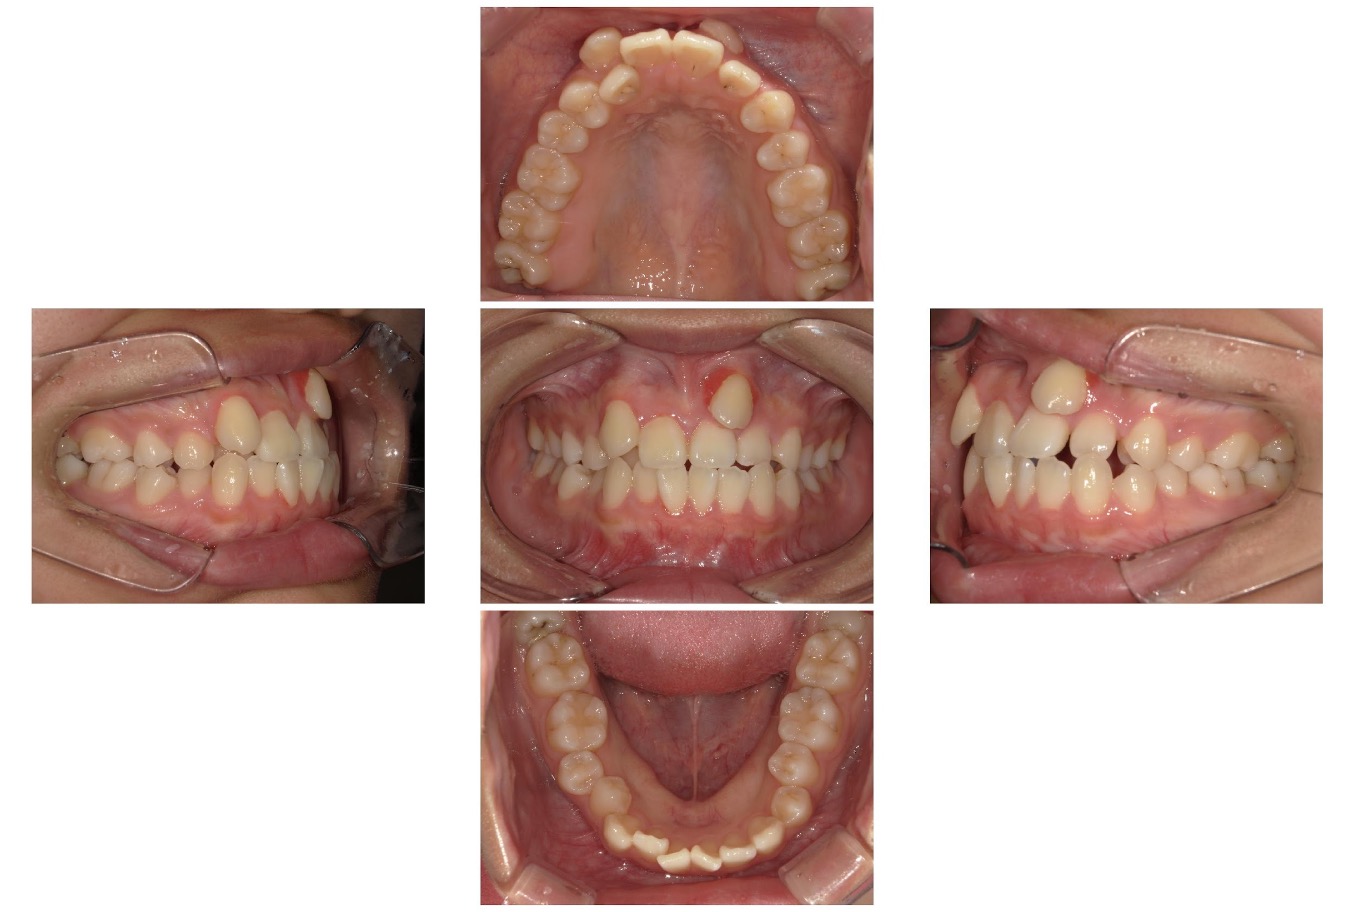

Case.03

治療前

治療後

| 主訴 | 上の八重歯と、上下の凸凹がきになる |

|---|---|

| 治療 期間 | 2年 |

| 治療費 | 880,000円 (税込968,000円) |

| 治療 内容 | インビザライン 右上3、左上3、右下4、左下4 抜歯 顎間ゴム |

| 治療の リスク | 1日に20時間以上装着しないと、予定通りに歯が動かないことがあります。装着後数日痛みがあります。 |